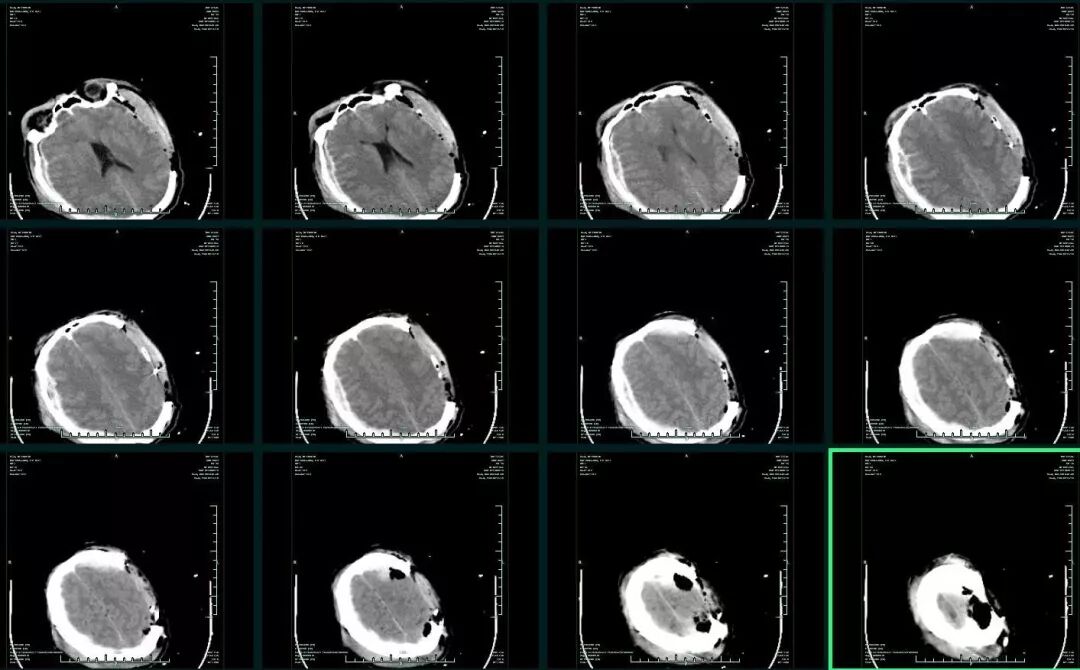

术后一周因右侧颅骨缺损处膨隆加重,复查CT示双侧硬膜下积液,左侧明显(图4),虽反复硬膜下积液抽吸和腰大池持续引流,但积液始终存在,意识状况也逐渐下降,出现深昏迷,GCS4分,左侧瞳孔0.35cm,右侧瞳孔0.2cm,对光反射均消失。一月后CT复查,硬膜下积液如前,左侧呈顽固性硬膜下积液。同时可见左侧额叶脑组织局限性粘连征象(图5)。

图4. 双侧血肿清除+去骨瓣减压术后1周CT提示左侧硬膜下积液,中线右偏。

图5. 术后1月,左侧硬膜下积液持续存在,反复经皮穿刺抽液无效。同时可见左侧额叶脑组织局限性粘连征象(图中黄色箭头)。